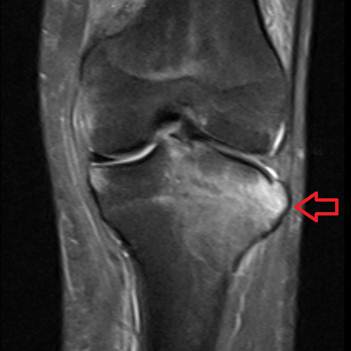

Bone edema is often diagnosed with a physical examination and imaging tests, such as an X-ray, MRI, or CT scan. These tests can help to determine the extent of the edema and the underlying cause.

Edema óseo alrededor de la rodilla | Alvarez López | Correo Científico Médico

Source: Correo Científico Médico – Infomed